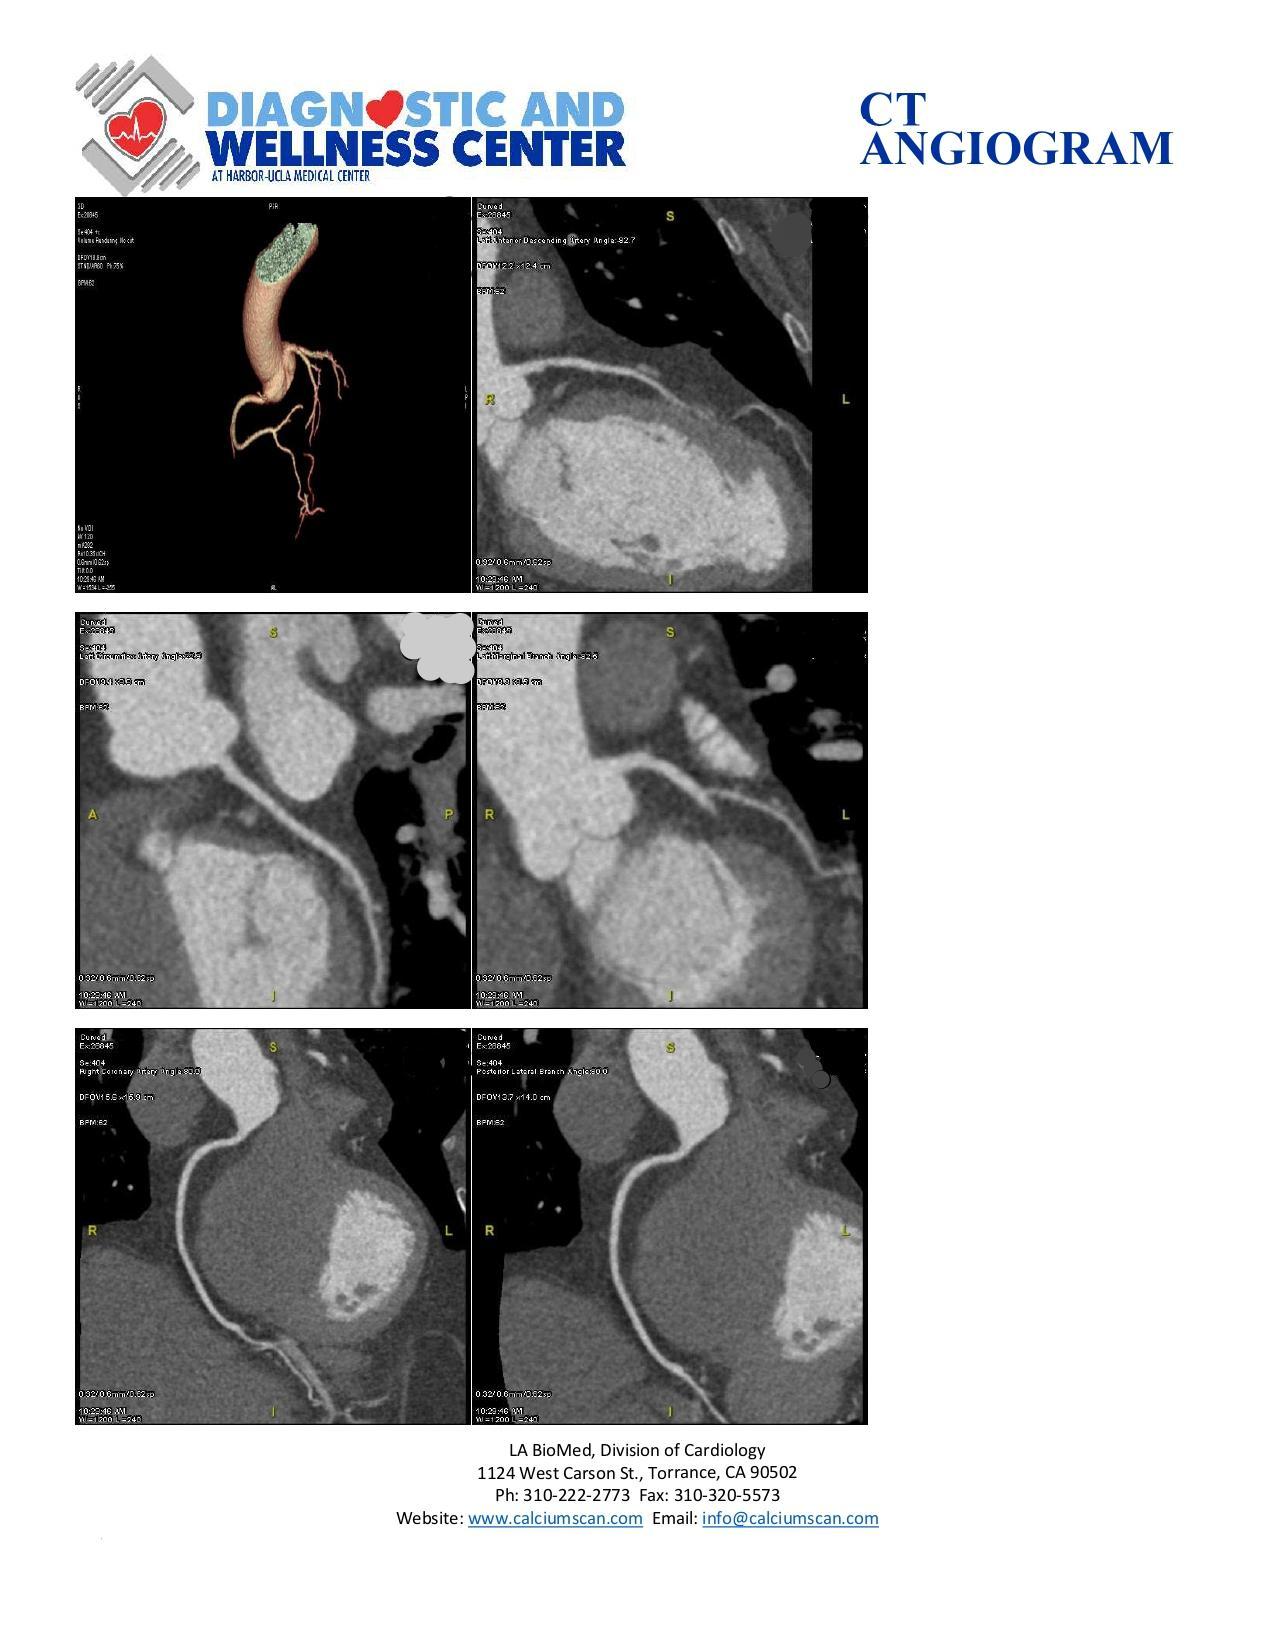

Dr. Arora refers patients for non-invasive CTA of the cornaries using the worlds fastest CAT scan machines to detect blockages in the heart arteries or carotid arteries in the neck for stroke.

Using the most modern technologies, Doctor Arora is, able to detect blockages in the heart arteries.